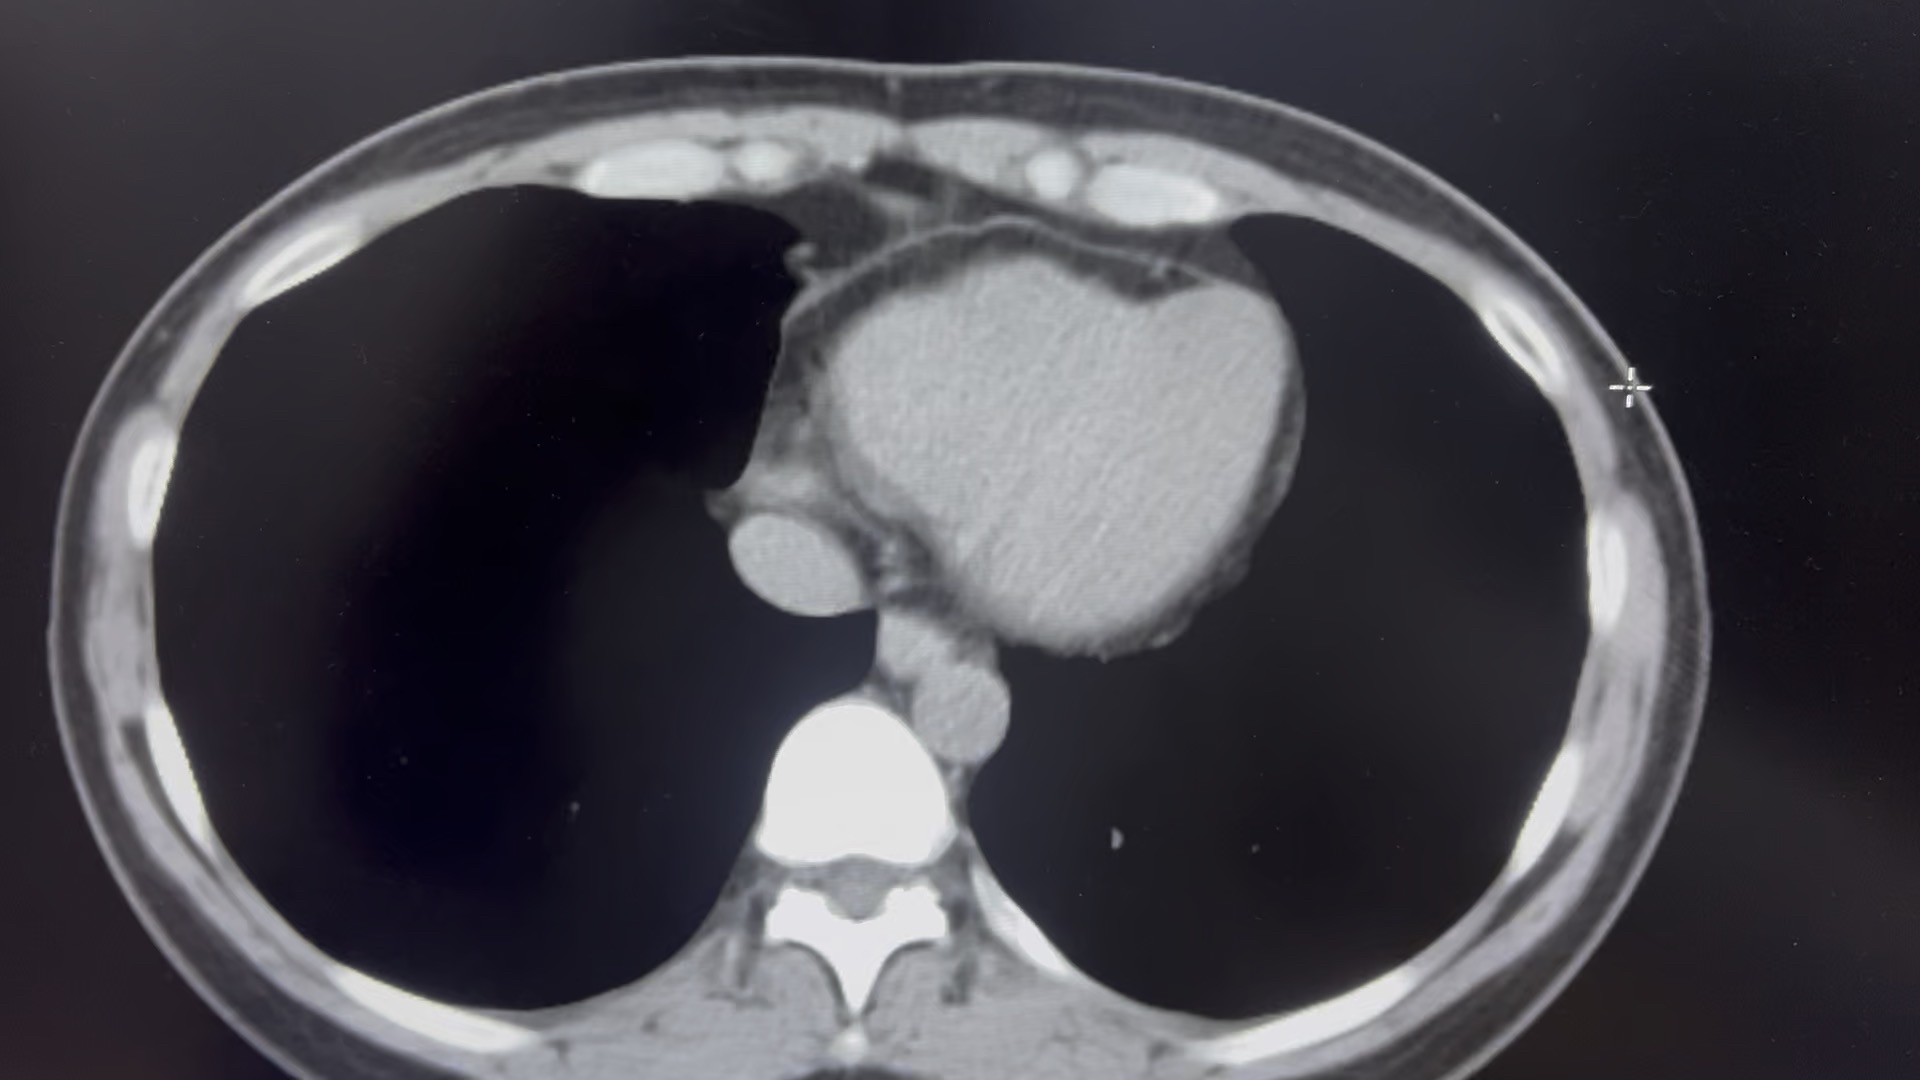

女44体检,附见肝左内叶似见管腔影,应该是肝左内叶局部胆管扩张,请老师请看看